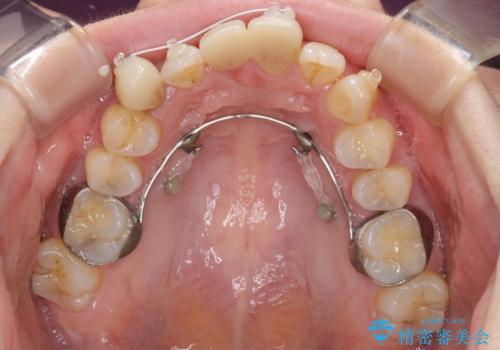

本来であれば積極的に小臼歯を抜歯して口元を下げても良いのですが、前歯を1本抜歯しないといけなくなったため、非抜歯矯正をインビザラインを用いて行うこととしました。

補助装置により上顎歯列を遠心移動させたため、非抜歯でしたが口元の突出感をある程度改善させることができました。